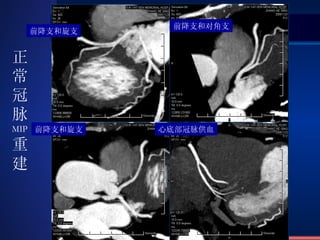

前降支和旋支 前降支和对角支 前降支和旋支 心底部冠脉供血 正常冠脉 MIP 重建

Coronary artery CTA MIP With Contrast Medium

VRT Recon. Normal Coronary artery CTA

前降支和旋支 前降支和对角支 前降支和旋支心底部冠脉供血 正常冠脉 MIP 重建